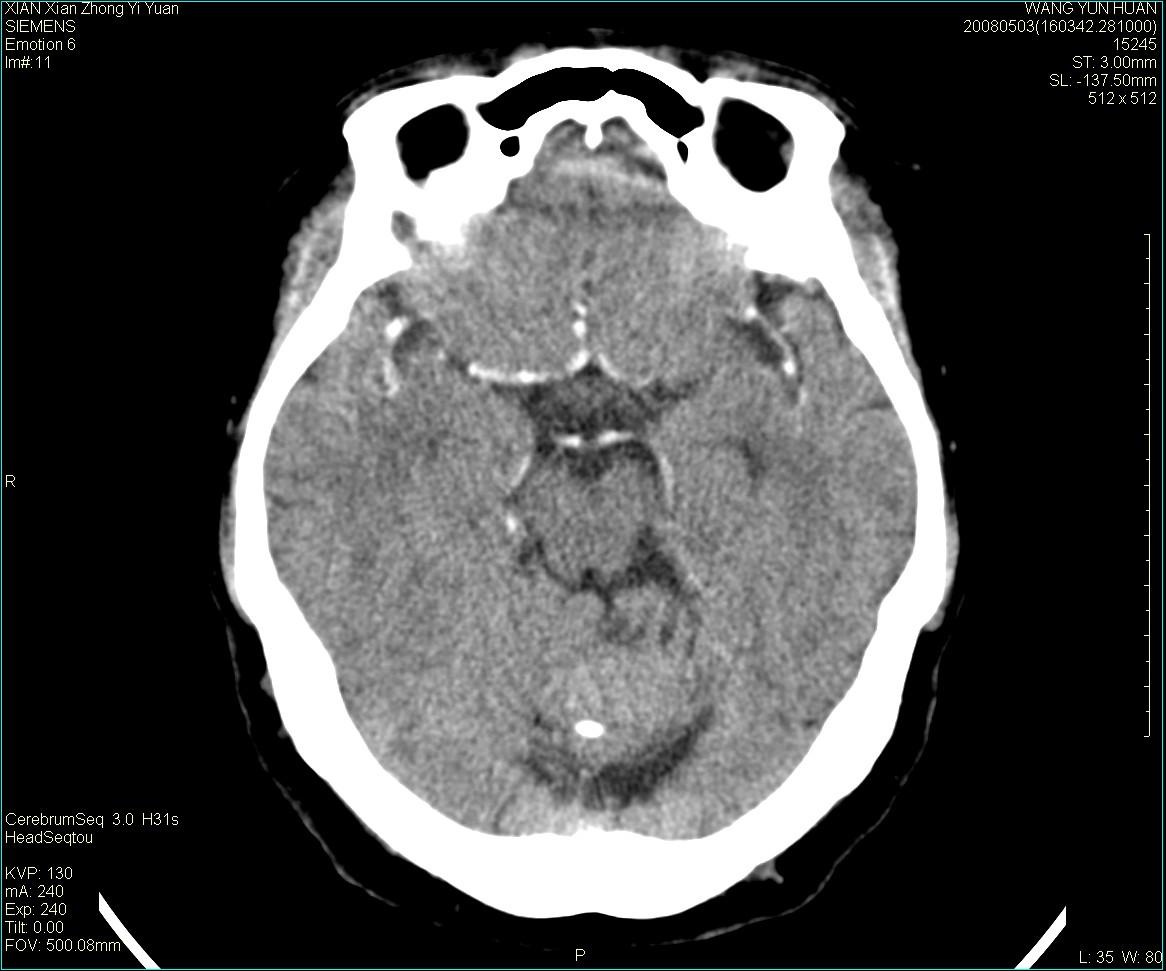

病灶显示轻度强化,ct增加4hu左右,大家看是什么肿瘤.

强化后动脉期及延迟2分钟,五分钟图像

小脑蚓部囊型肿块,内有实性结节及钙化点。增强后囊壁及结节轻度强化。

考虑蚓部星形细胞瘤(ⅱ级可能性大)。

小脑蚓部肿块,周围无明显占位效应及水肿带,增强轻度强化,考虑低分级星形细胞瘤。